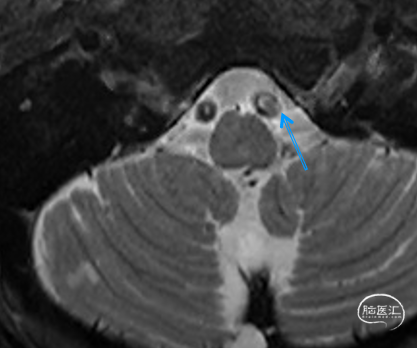

➢2024.07.10 MR:

核磁共振提示发病机制穿支事件+低灌注

高分辨核磁提示左侧椎动脉V4段不稳定斑块

患者高分辨核磁提示患者左椎动脉V4段-基底动脉闭塞,管壁不稳定斑块,开通过程中可能引起斑块脱落导致远端栓塞,因此手术重点需要兼顾远端血管保护及血管成型。应用COSIS技术,Syphonet®取栓支架保护远端正常基底动脉,同时还可以作为锚定装置,保留手术通道,减少器械交换次数,增加手术安全性。